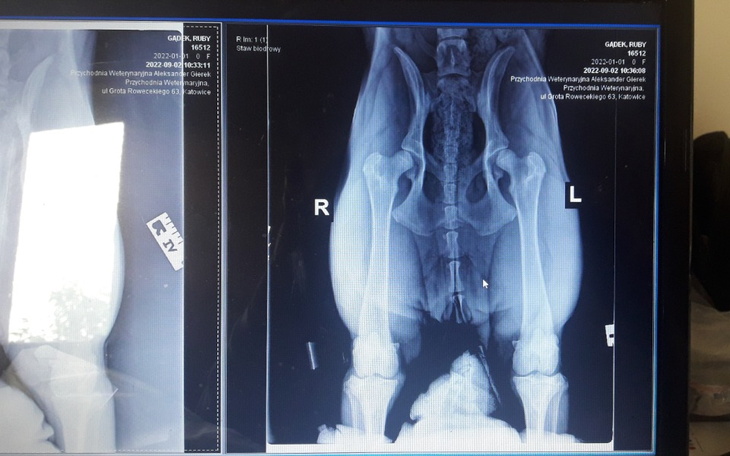

Moja 8 miesięczna Ruby sunia owczarka niemieckiego potrzebuje bardzo pilnie operacji stawu biodrowego dwóch łapek. Operacja dwóch stawów biodrowych to 9000,00 zł. Jeżeli operacja się nie odbędzie to konieczne będą endoprotezy stawów biodrowych, która jest kilkadziesiąt zł droższe, albo Ruby resztę swego życia będzie miała ograniczony ruch i będzie musiała brać leki przeciw bólowe. Proszę pomóżcie Ruby stanąć na zdrowych łapkach,